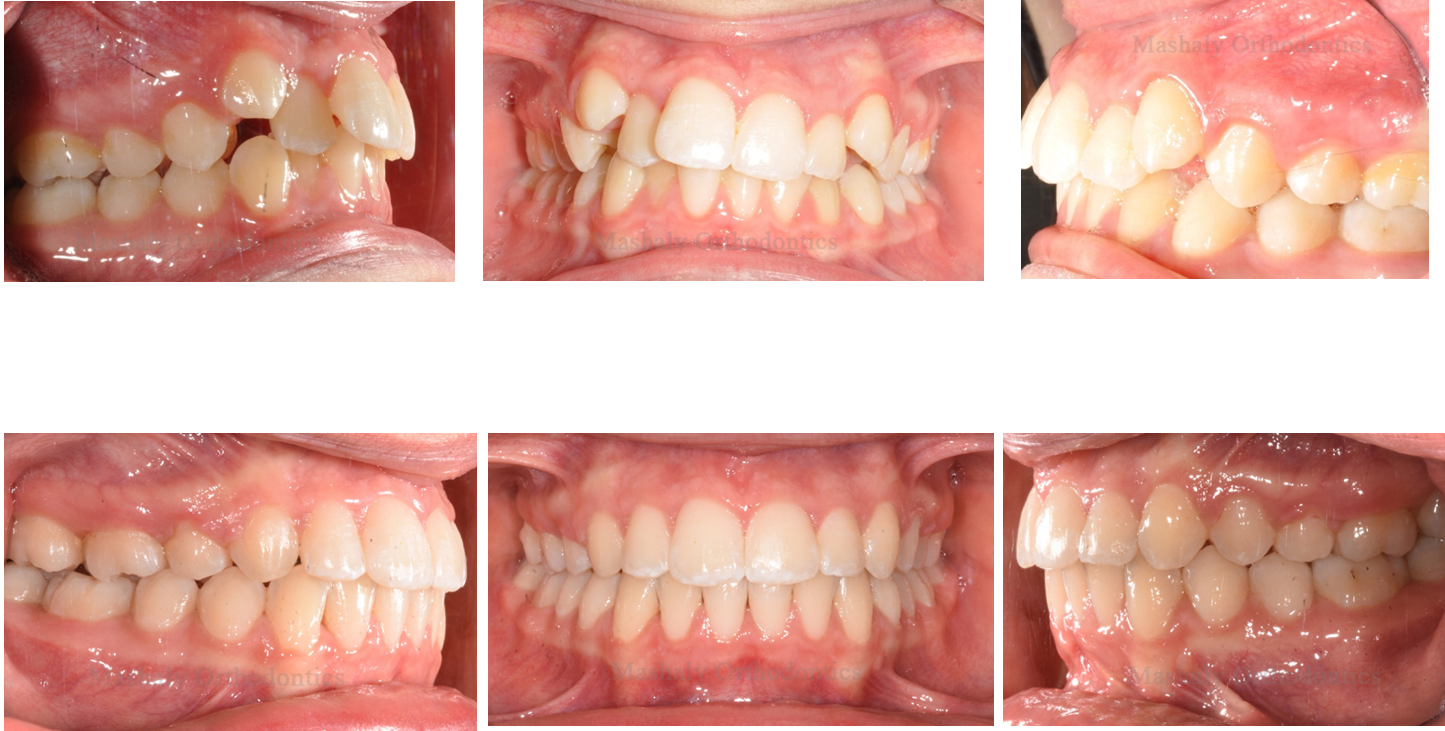

Orthodontics is a dental specialty that helps treat misalignment of teeth, malocclusion

(improper bite), and other related issues. Orthodontic treatment goes beyond addressing cosmetic concerns and is also used to treat various medical conditions such as impacted teeth and other dental problems.